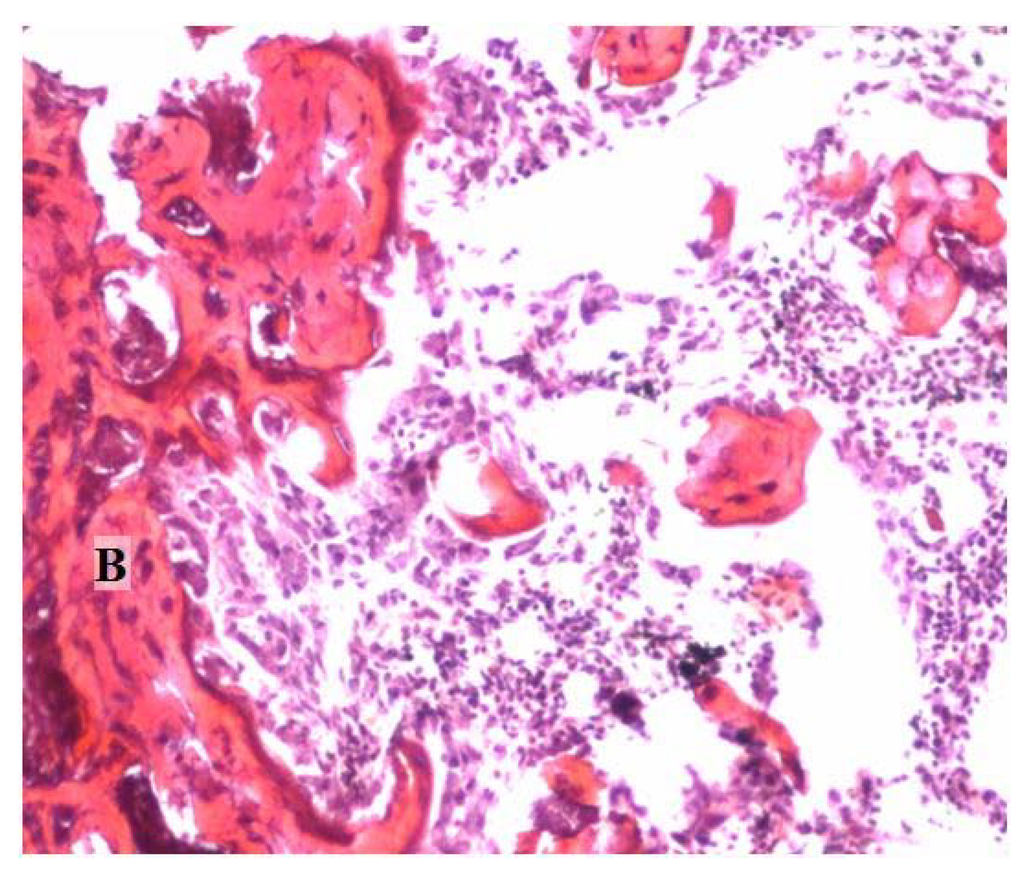

For group a, the radiographic evaluation of the hydroxyapatite-tricalcium phosphate-calcium sulfate discs (HAP:TCP:CS 30:60:10) demonstrated some bone formation outside the active implant; however, the control implants remained intact (Table 1, Figure 3a). The measurement area was significantly higher for the active implants compared to the controls (p < 0.01). The harvesting analysis indicated that this new formation was bone-like. The histological evaluation demonstrated that endochondral bone formation occurred in the active sample and not in the control sample (Figure 4a, b).

For group d (calcium sulfate hemihydrate discs), the radiography analysis revealed some new bone formation, and significant differences (p < 0.01) were apparent between the active and control groups (the control group had visibly resorbed) (Table 1, Figure 3b). However, the harvesting and histological analysis showed that no new bone was found in the samples (Figure 4c, d).

For group f (calcium sulfate dihydrate—stearic acid), the radiographic analysis and harvesting analysis revealed new bone formation in the active implant group (Table 1, Figure 3c). The difference between the active implants and the controls was statistically significant (p < 0.01). Also, histological analysis revealed clear bone formation and mature and calcified cartilage in the active sample (Figure 4e). No visual bone formation was apparent in the control sample (Figure 4f).

Figure 4. Histological examination showing the new bone formation and the implant response in the mouse pouch model using different carriers with the reindeer bone protein extract: (a) HAP/TCP/CS 30:60:10 active; (b) HAP/TCP/CS 30:60:10 control without bone protein extract; (c) CS hemihydrate active; (d) CS hemihydrate control; (e) CS dihydrate + stearic acid active; and (f) CS dihydrate + stearic acid control. C = calcified cartilage cells, B = bone, M = muscle, F = fibrotic tissue, and I = implant carrier. (Original magnification 10×).